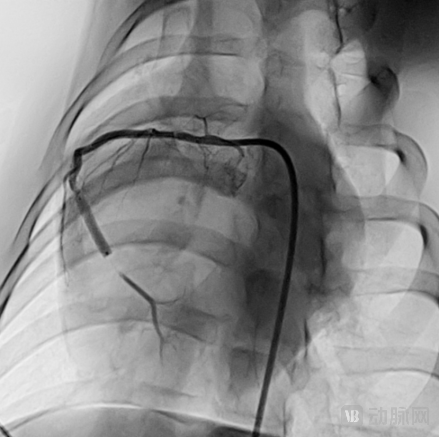

两组9个月靶病变节段内晚期管腔丢失均数差在FAS数据集、PPS数据集下 95%CI 的上限均小于方案规定的非劣效界值 0.195mm,非劣效成立。而且整个临床试验,恒言自灌注药球平均扩张时长比对照组更长。如下图: